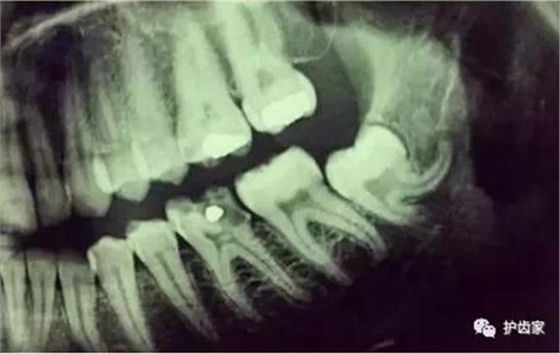

拍片是為了了解智齒周圍情況,也是為了了解智齒結(jié)構(gòu),牙根結(jié)構(gòu)千變?nèi)f化,有可能是融合成一個(gè)根,也可能是八爪根。不同牙根不同位置及方向,只有通過拍片來確認(rèn)。

拍片也為了了解下頜神經(jīng)與智齒的關(guān)系,一般離得近,有醫(yī)療風(fēng)險(xiǎn)的,基本沒有醫(yī)生愿意拔,現(xiàn)在沒人為了幾百元,賠上自己的職業(yè)生涯。誰都怕拔智齒,敲打智齒,一不小心,碰到神經(jīng),就攤上大事了。有理都說不清。

通過拍片可以了解牙齒本身:生長方向,牙根數(shù)目,牙根是否彎曲,膨大等。

與重要解剖結(jié)構(gòu)的位置關(guān)系:如上頜磨牙與上頜竇的關(guān)系;下頜磨牙與下頜神經(jīng)管的關(guān)系;兒童在混合牙列期恒牙與乳牙胚的關(guān)系等??梢詼p少拔牙的風(fēng)險(xiǎn)。